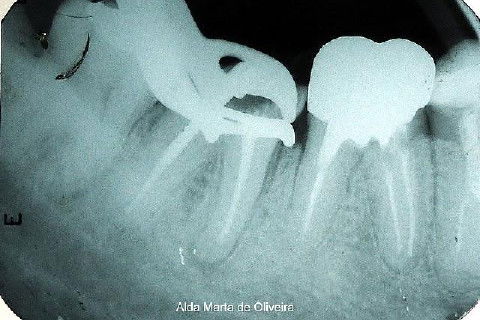

Paciente de 46 anos, encaminhado por uma colega para que eu instalasse um pino e fizesse um núcleo de preenchimento no dente 47.